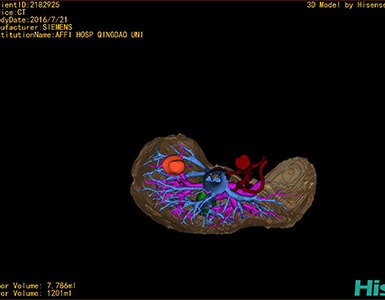

将0.625mm双源薄层CT资料的静脉期和动脉期Dicom格式文件导入海信CAS系统。

通过调节窗宽窗位调整CT序号,对肿瘤,肝实质,胆囊,下腔静脉,肿瘤,肝动脉、门静脉及肝静脉等进行三维重建;系统自动计算肿瘤体积和肝脏体积。

模拟手术操作,自动计算切除肿瘤体积。肝脏体积为1201ml,肿瘤体积为7.786ml,肿瘤体积为肝脏体积的0.6%,通过比对40-50岁正常肝脏体积为1368.38±279.24 ml,肝脏可先进行保守治疗,肾脏进行部分切除术。

术前手术方案的规划。

术前三维重建:

重建图片